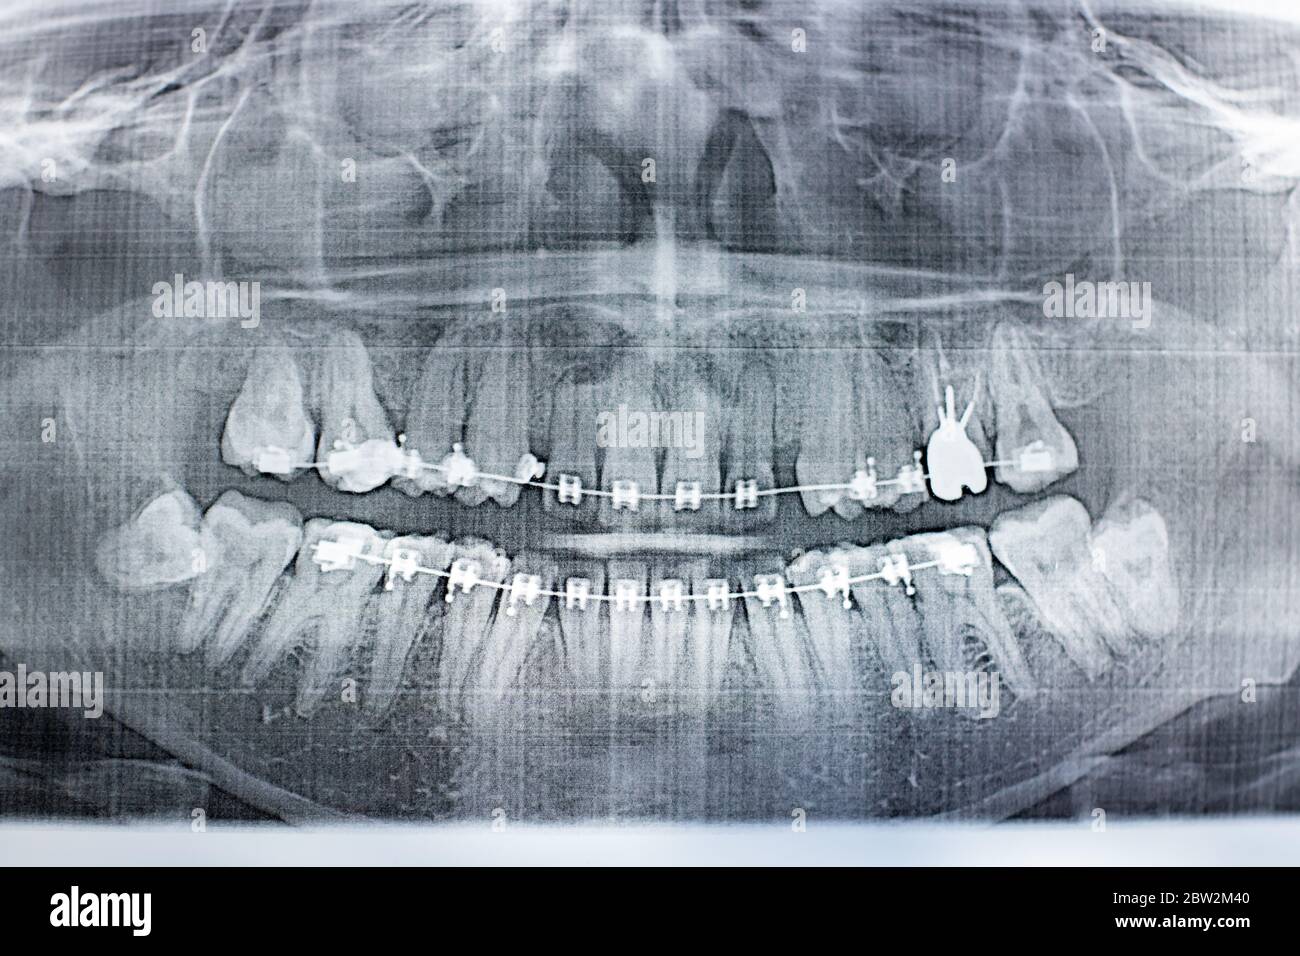

Panoramic X-ray Image Of Teeth And Mouth With Wisdom Teeth | Parkview

Panoramic Dental X-ray With Superior Upper Wisdom Tooth (eight Tooth

revealdiagnostics.comPanoramic Dental X-ray - 32 Teeth - 4 Wisdom Stock Photo - Image: 39446538

revealdiagnostics.comPanoramic Dental X-ray - 32 Teeth - 4 Wisdom Stock Photo - Image: 39446538

www.dreamstime.comteeth ray panoramic wisdom dental mouth year old visible missing male full stock

www.dreamstime.comteeth ray panoramic wisdom dental mouth year old visible missing male full stock

Orthopantomography, OPG X-ray DR Digital Wisdom Teeth Stock Photo - Alamy